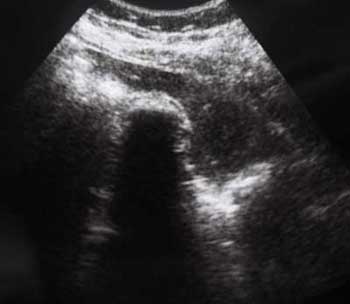

Похожий случай. Молодой мужчина, врач, длительные терпимые боли в правом подреберье.

???

2.По второму случаю можно было бы просто подумать о гиперкинезии ж.пузыря,который сокращается и "от глотка слюны".Но,прочитав эту фразу:"In patients with hilar cholangiocarcinoma and complete obstruction of both rigt and left hepatic ducts,extrahepatic bile ducts and the gollbladder appear empty(colapsed)",учитывая сложность выявления "малых" опухолей печени методом УЗИ,я думаю,что надо сделать КТ.

Похожий случай сегодня: